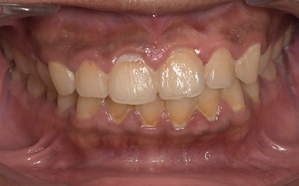

健康な歯ぐきの特徴

健康な歯ぐきは、綺麗なサーモンピンク色で、歯と歯の間が三角形でうまっています。近くで見ると、表面にみかんの皮のような細かなつぶつぶがあります。痛くない程度の力で歯ブラシの毛先を歯ぐきに当てて磨いてみましょう。出血が起こらなければ、健康な状態だといえます。

健康な状態の歯ぐきの写真